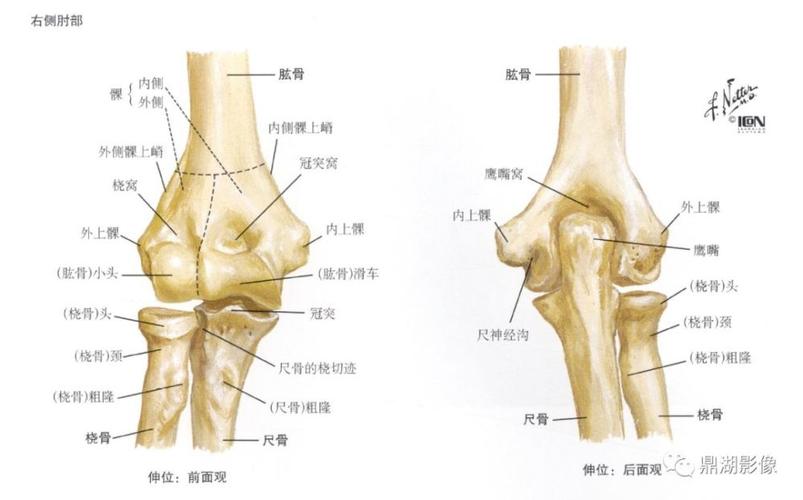

肘关节x线解剖

肘关节x线解剖及常见骨折诊断

正常肘关节x线解剖

2019--8-26 肘关节x线解剖学

肘关节解剖解剖图

肘关节解剖